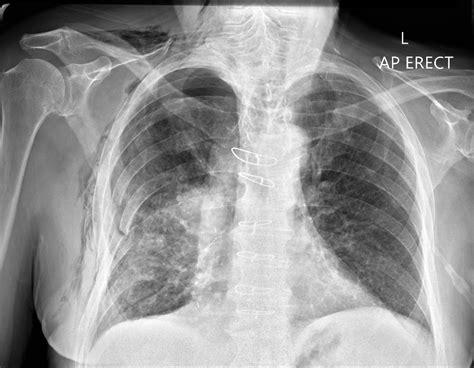

• Malignant Lesions: These are cancerous and can metastasize to other organs. Common types include osteosarcoma, Ewing sarcoma, and chondrosarcoma.

• Cancer: Both primary bone cancers (e.g., osteosarcoma) and metastatic cancers (e.g., breast cancer spreading to the bone) can cause bony lesions.

• Imaging Studies: X-rays, CT scans, MRI, and bone scans are commonly used to visualize the lesion and determine its characteristics.

• Radiation Therapy: Used to shrink malignant lesions and reduce pain.

• Chemotherapy: Systemic treatment for malignant lesions to destroy cancer cells.